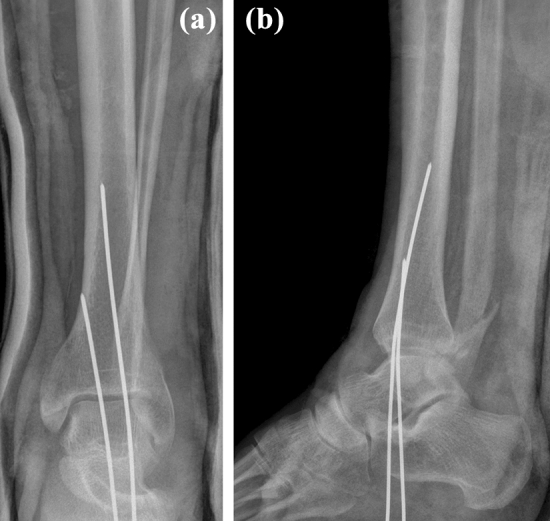

The following attempt at closed reduction under intravenous analgesia failed. The patient was admitted to the hospital and while waiting for reduction under general anesthesia the pain and swelling in his left foot increased and he began to develop paresthesia in the plantar aspect of the left forefoot. Closed reduction under general anesthesia was performed at the night of admission, 8 h after the injury. According to the treating surgeon, reduction was successful (Fig. 2). Following reduction, the pain subsided as a result of administration of analgesics. On the next morning, 15 h after the injury, the patient underwent CT examination, including 3D reconstructions. Although the results confirmed a proper diagnosis of a BF, they also showed failure of reduction. A posterior malleolus (PM) fracture representing type 3 of the Bartoníček-Rammelt classification [12] was detected. The proximal fragment of the fibula was entrapped behind the nondisplaced posterolateral part of the PM fragment (Fig. 3).

Fig. 2.

Radiograph after unsuccessful closed reduction under general anesthesia showing persisting a overlap of the distal tibia and fibula, and b tibiofibular dissociation